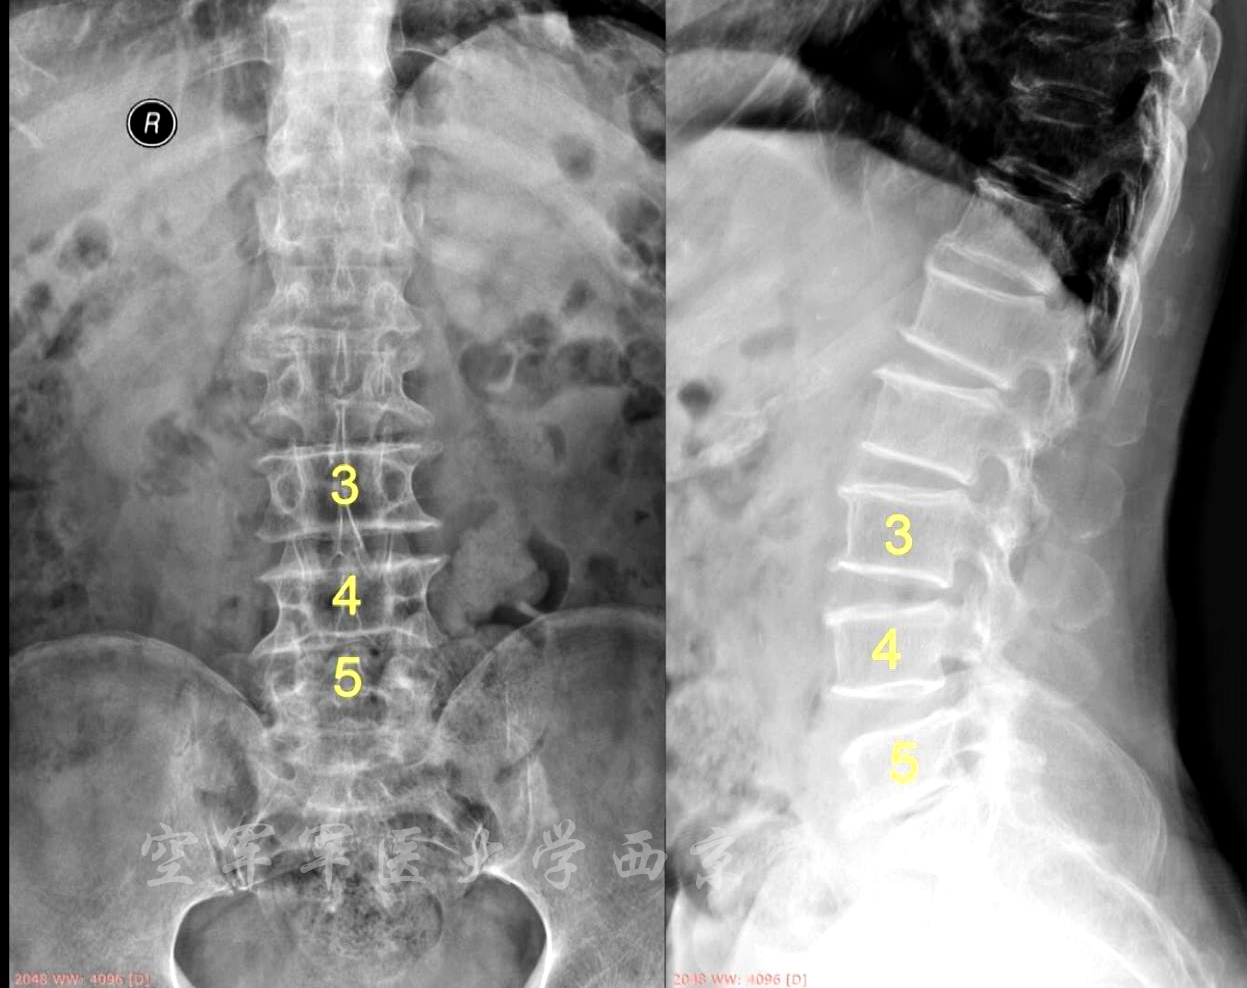

术前X线正侧位片

术前MRI